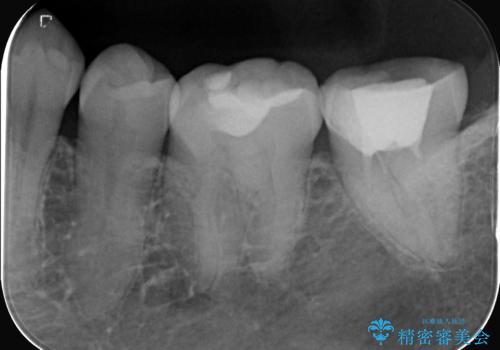

- 患者様は、他院で根管治療を受けたものの、違和感が続くため「しっかりとした治療を受けたい」とのご希望で来院されました。診査の結果、根管内の感染が完全に除去されておらず、根の先に炎症が残っている状態でした。そこで、精密根管治療を行い、感染源を徹底的に除去する計画を立てました。マイクロスコープを使用し、4回の治療で根の内部を清潔にし、最終的にしっかりと密封することで、長期的な安定を目指しました。

治療は、まず根管内の古い充填材を取り除き、感染部分を徹底的に洗浄・消毒することから始めました。ラバーダム防湿を使用し、治療中の細菌感染を防ぎながら、マイクロスコープを用いて根管の細部まで確認しながら処置を進めました。4回の治療で感染の除去と根管の封鎖を行い、最終的に土台を立てて被せ物の準備を整えました。患者様からは「違和感がなくなり、噛んでも痛くない」と喜びの声をいただきました。